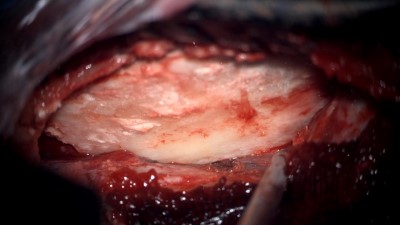

Intraoperative photo demonstrating the operative approach. A right temporal craniotomy has been made and the covering of the brain, the dura mater, is being dissected off of the base of the skull. Orientation: this is the right side of the head; the ear is just off the top of the frame (green star(*)), the nose is to the left, the back of the head the right, and the top of the head is toward the bottom.

Intraoperative video demonstrating the dissection of the encephalocele. Note the band of tissue extending from the skull base defect on the top of the image through the dural defect toward the bottom. This is the encephalocele.